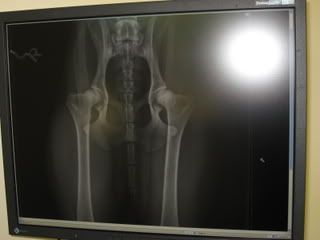

Tja, die HD in Ungarn immer noch ein großes Thema, aber leider sehen es die ungarischen Züchter ja nicht ein!